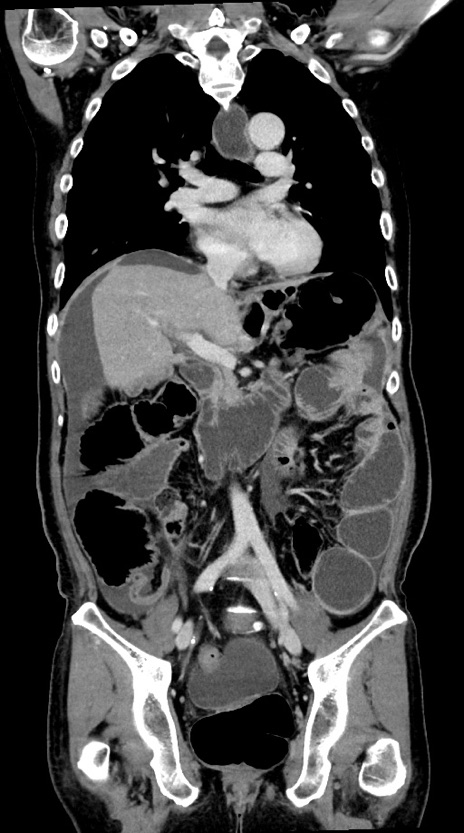

横断像

【症例】60歳代男性

【現病歴】胃癌にて胃全摘後。食思不振が悪化し、夜中に嘔吐することがある。

【既往歴】胃癌、胃全摘、脾摘、胆摘後

【データ】WBC 5900、CRP 10.56